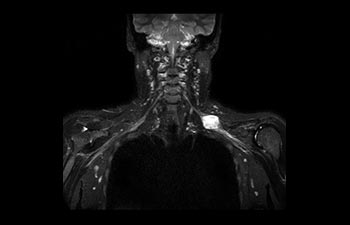

Find the right clinical applications for your needs

See all Ingenia Prodiva 1.5T coils